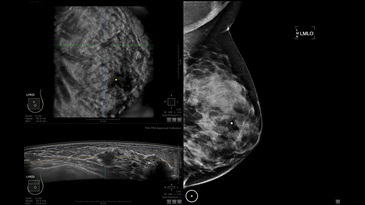

GE INVENIA ABUS – это современный УЗИ аппарат, который создан для точной и эффективной диагностики сканирования с высокой плотностью молочных желез. Выявляемость патологий раковых и предраковых стадий заболевания составляет 55%, что в конечном счете позволяет ставить врачу точные и своевременные диагнозы. Традиционные методы использования маммографии не показывают такой выявляемости, ограничиваясь лишь 3-38%.

УЗИ-аппарат GE INVENIA ABUS позволяет проводить максимально операторонезависимые процедуры, что значительно снижает риск неправильной постановки диагноза и сопутствующие издержки на обработку информации. Система готовит отчет в течение 3-х минут после сканирования, это безусловное преимущество по сравнению с обычным УЗИ сканером.

• Получение изображений в поперечной плоскости (в реальном времени) и в коронарной плоскости (статическая, для указания нахождения соска)

• Отображение объемных 3D ультразвуковых изображений, которые состоят из традиционных поперечных и воссозданных коронарных и сагиттальных проекций

• Стандартизованная ориентация изображения: «толстый срез» в коронарной плоскости; поперечная; сагиттальная плоскость; радиальный и антирадиальный поворот изображения; просмотр исключительно области интереса